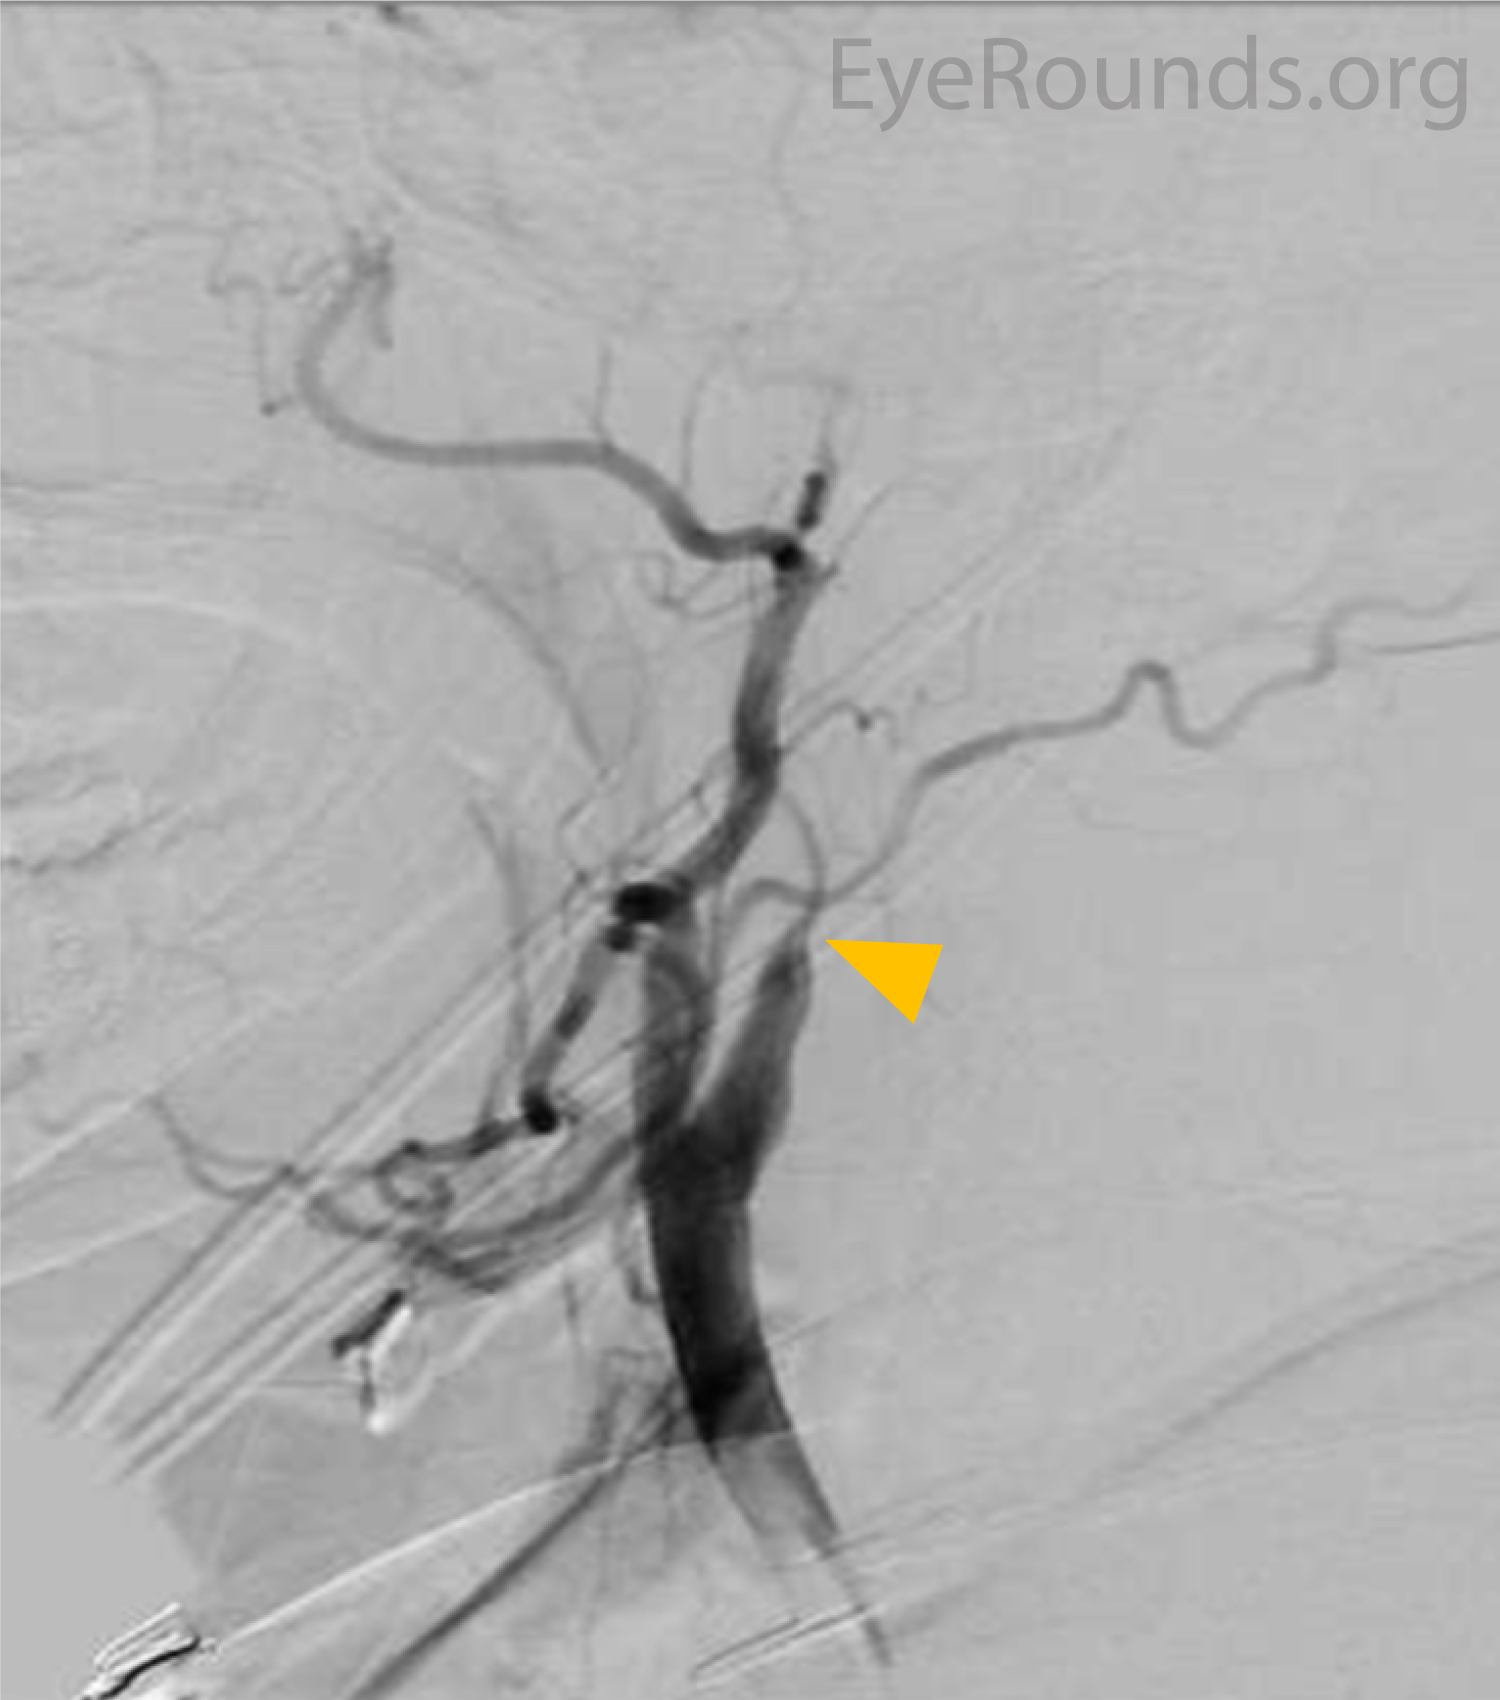

Cerebral angiogram

Figure 4: Cerebral angiogram revealed 99.5% occlusion of the right cavernous segment of the internal carotid (yellow arrow) artery, with reconstitution via the right ophthalmic artery via a meningo-ophthalmic variant. The left internal carotid artery was 100% occluded at the petrous segment (not shown).